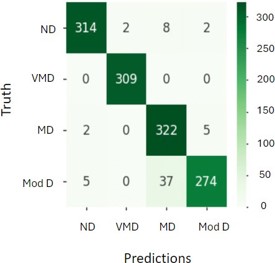

F. Confusion matrix: A confusion matrix is a tool used in DL and ML, specifically for classification issues, to monitor and evaluate algorithm performance. It does this by comparing the anticipated and actual classes as shown in figure 12 [23].

Where,

ND is non-demented.

VMD is Very Mild Demented.

Mod D is Moderate Demented.

MD is Mild Demented.